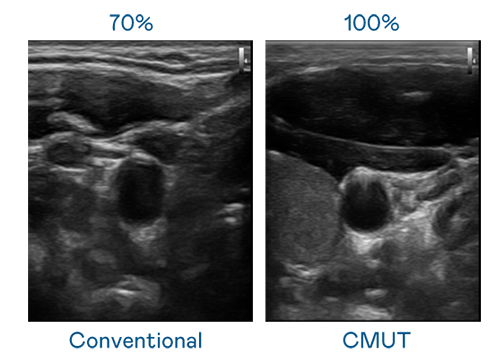

CMUT 技術是一種用電容式微機電元件來產生超音波訊號的技術。與傳統 PZT 壓電式技術相比,CMUT 頻寬增加 30%,更寬頻的超音波訊號讓影像解析度大幅提升,是實現高影像品質醫療超音波掃描、促進精準醫療發展的關鍵技術。

超音波影像的解析度高低,首先取決於探頭能發出的訊號頻寬。SA视讯 CMUT 可提供高清晰的超音波訊號,提供高頻寬、高靈敏度、影像紋理細節更高的超音波影像,協助醫護人員縮短影像判讀時間及利用精準的醫療影像進行診斷。